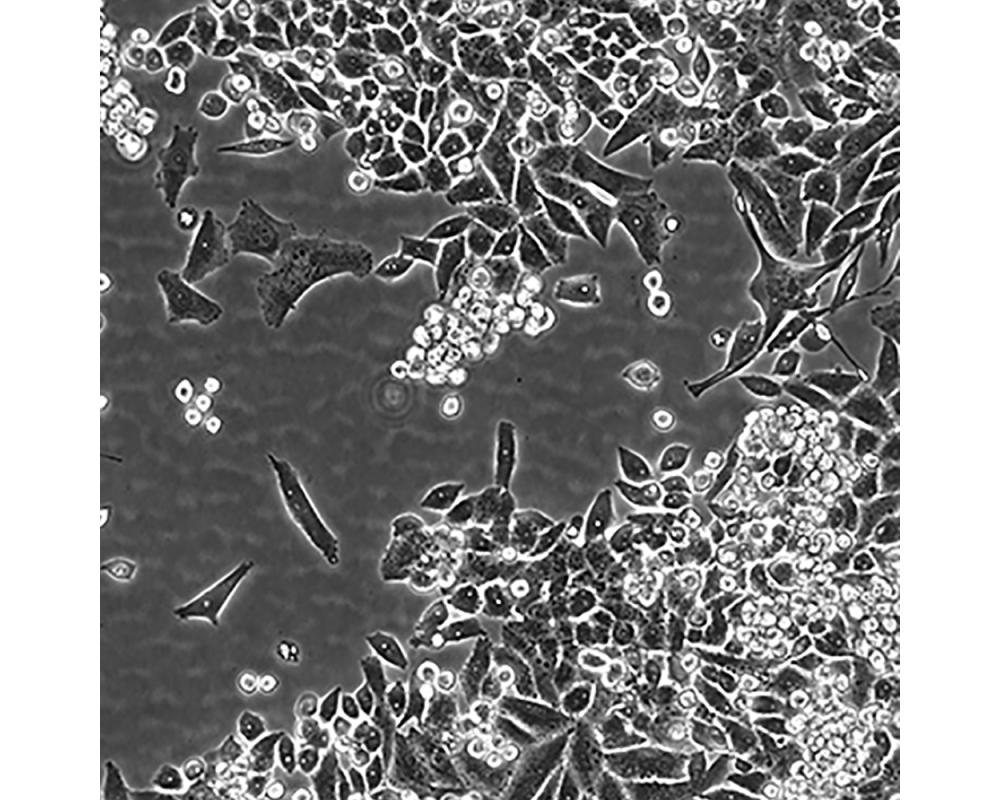

MiaPaCa-2

中文名稱 人胰腺癌細胞

組織來源 胰腺導管癌;男性

生長特性 貼壁